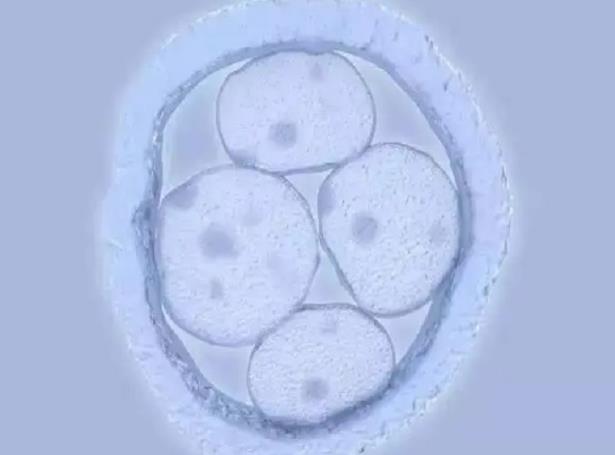

3.改善卵泡發(fā)育同步化,爭取得到更多的同步發(fā)育的成熟卵泡。

雖然女人一生的卵子數(shù)量是有限,正常來講每個月都會排出很多卵子,只有一個卵子生長成熟,其他卵子會被抑制成熟并使其消亡。降調(diào)其實只是把列入消亡的卵子拉回生長行列,使其生長成熟。即便我們不把其利用起來,它們也是會被排出并消亡!